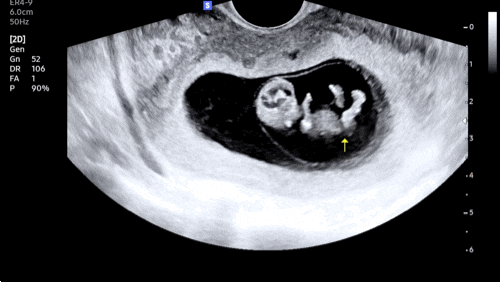

[임신 12주차]증상,드디어 첫 정밀초음파, 성별❣️

엘디와 함께한지 벌써 12주 째! 안정기 시작으로 불리우는 주수이고 나는 드디어!!! 크녹산과 이별했다~~~ ...